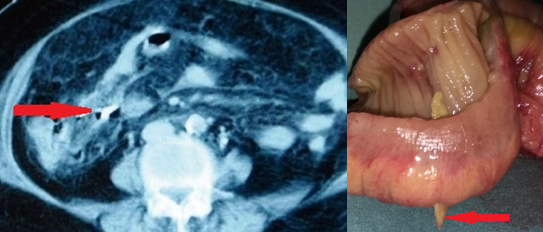

Red arrows — transition point. Multiple air-fluid levels (Courtesy Dr. V. Penopoulos)

The two metastatic foci causing stenosis and bowel obstruction are clearly visible (Courtesy Dr. V. Penopoulos)